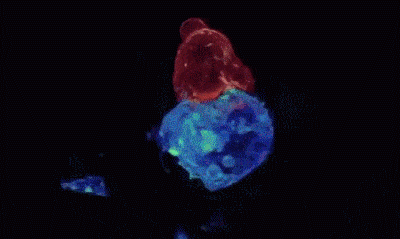

原理:这两张动图都来自一项研究记录下的延时摄影,其中展示的是细胞毒性T细胞(cytotoxic T lymphocytes)寻找并摧毁癌细胞的过程。首先,T细胞(上图红色和下图中绿色)结合在癌细胞(蓝色)膜表面的特殊分子上。然后,它部分包裹在癌细胞上,并且用自己的蛋白“炮弹”(绿色细胞中的红色)“轰炸”癌细胞。细胞毒性T细胞释放的穿孔素可以破坏细胞膜,而颗粒酶进入目标细胞之后,可诱发细胞凋亡。% |: t' V  Q' _  f% C7 [

花絮:细胞毒性T细胞也被称为“杀手T细胞”(killer T cell),它们可以辨别特定的抗原,识别并杀死那些癌变、受病毒感染的异常细胞。不过,这道天然的免疫屏障并不完美,癌细胞有时候并没有表达出足够被T细胞识别的特征,清除工作也就无法进行了。而现在,研究者们也在探索弥补天然免疫过程不足的方法,帮T细胞更好地杀灭癌症(更多阅读:编辑细胞,激活免疫,斩杀癌症)。